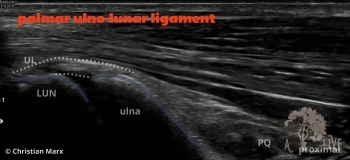

carpal ligaments